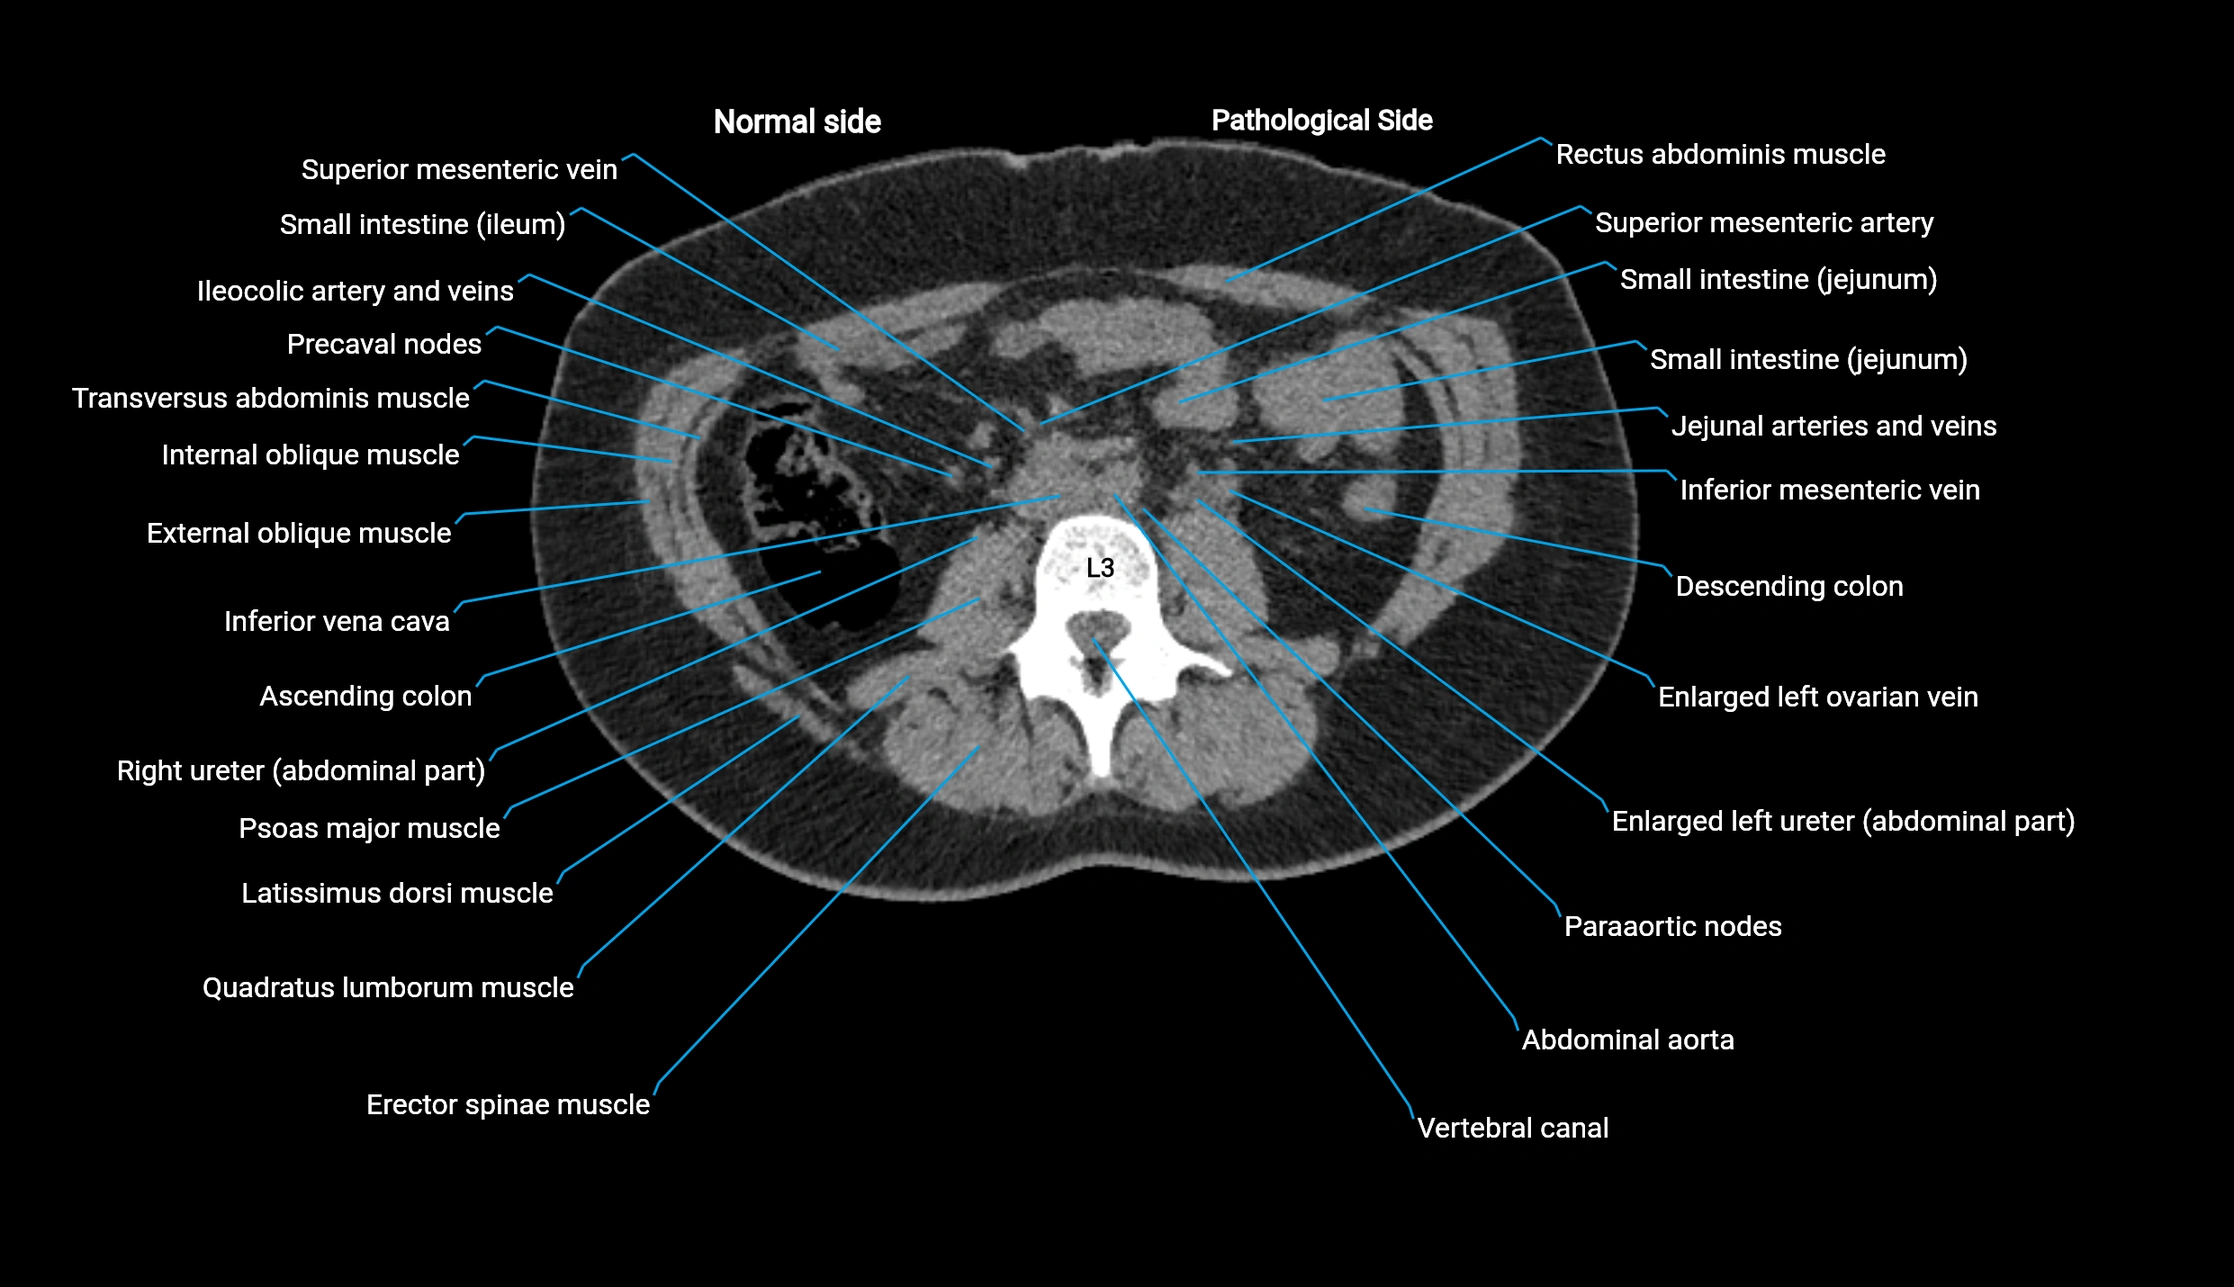

CT image

image